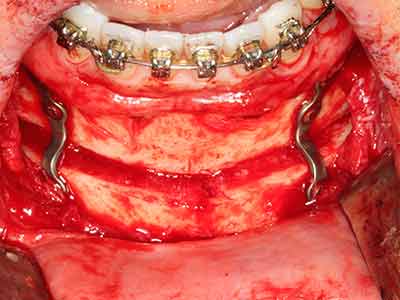

El tejido óseo no solo tiene un contenido puramente mineral, sino que también presenta una importante proporción de fibras de colágeno. Esto no solo garantiza una buena resistencia a la presión, sino también una cierta flexibilidad, que puede aprovecharse para la realización de aumentos. En la plastia de expansión clásica a efectos de una partición ósea, la cresta maxilar atrofiada se divide en su eje longitudinal y, tras alcanzar una profundidad de osteotomía suficiente, se extiende con cuidado (fig. 13-16), en un caso ideal sin desperiostizar de forma visible el maxilar (Brugnami, Caiazzo et al. 2014, Stricker, Fleiner et al. 2014). Los sistemas de tornillos y placas con distancia de expansión creciente han demostrado su eficacia para distanciar entre sí las dos tablas óseas por debajo del umbral de rotura. Por regla general, se requieren anchuras de hueso residual de al menos 3 a 4 mm (Chiapasco, Zaniboni et al. 2006) para garantizar una flexibilidad y una cobertura ósea suficientes de los implantes que van a incorporarse. En caso necesario, una osteotomía de descarga vertical unilateral o bilateral puede mejorar la flexibilidad. Como alternativa a la técnica clásica se ha descrito una combinación con otras técnicas de aumento, sobre todo en la parte bucal.

Con el uso de sierras piezoeléctricas la división se efectúa de forma especialmente cuidadosa y sin pérdidas importantes de las dimensiones, por lo que no se han encontrado diferencias significativas entre los implantes realizados en el maxilar dividido y en la cresta alveolar no deficitaria (Chiapasco, Zaniboni et al. 2006, Danza, Guidi et al. 2009). No obstante, precisamente en la partición profunda y limitada de forma local, es preciso asegurarse de que exista una adecuada irrigación por agua para evitar que se produzcan sobrecargas térmicas en las áreas de osteotomía apical.

Como ya se ha demostrado en el pasado, básicamente cualquier procedimiento de cirugía de hueso representa una posible indicación para la cirugía piezoeléctrica. Así, la preparación del segmento móvil en la osteogénesis de distracción (fig. 23-25) y en la osteotomía de sándwich puede realizarse con piezas especiales, sin poner en peligro el suministro sanguíneo de la parte crestal, que resulta esencial para el éxito de ambas técnicas (González-García, Diniz-Freitas et al. 2008).